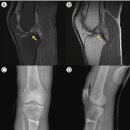

수술 후 환자는 다시 본원에 내원했고, 수술 후 회복과 재활을 위해 침구 치료 및 한약을 적극 활용했다. 이 과정에서 트라마돌과 같이 마약성 진통제로 분류될 수 있는 화학 약물 사용도 최소로 줄일 것을 권고했다. 결과적으로 환자의 우측 무릎 상태는...